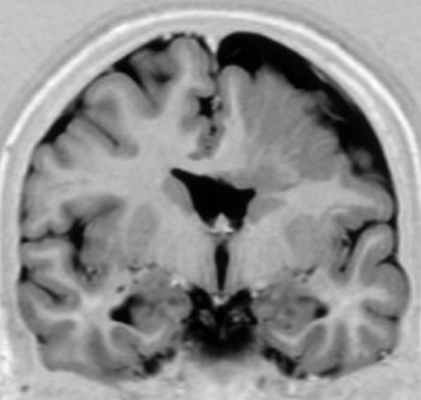

• Гипертрофированное БВ часто имеет гиперинтенсивный сигнал на T2-ВИ/FLAIR (ускоренная миелинизация)(а) На рисунке коронального среза показано увеличение объема большого полушария головного мозга вследствие его чрезмерного роста. Обратите внимание на смещение срединных структур, избыточное количество белого вещества (БВ), утолщение и сглаженность/дисморфизм извилин, а также аномальную конфигурацию ипсилатерального переднего рога.

(б) Бесконтрастная КТ, аксиальный срез: у четырехлетней девочки с некупируемым судорожным синдромом определяется увеличение правого большого полушария, ипсилатеральной 1 /2 мозгового черепа в сочетании с увеличением объема белого вещества лучистого венца, ипсилатерального мозолистого тела, а также свода мозга. Кроме того, отмечается латеральное смещение серпа мозга. (а) МРТ, Т2-ВИ, аксиальный срез: у того же пациента определяется увеличение размеров полушария в сочетании с повышением сигнала от его БВ, а также увеличение деформированного правого желудочка и утолщение диспластичной коры.

(б) МРТ, Т2-ВИ, корональный срез: определяются увеличение размеров правого полушария, а также латеральное смещение серпа мозга. Передний рог ипсилатерального бокового желудочка деформирован и заострен. Изменения соответствуют классической гемимегалэнцефалии (ГМЭ).в) Патология:

Гемимегалэнцефалия (ГМЭ) или унилатеральная мегалэнцефалия — дисплазия головного мозга, обусловленная унилатеральными нарушениями нейронной миграции и пролиферации, результатами которых является одностороннее диспластическое увеличение одной из гемисфер (В.А. Чадаев и соавт., 2003). Гемимегалэнцефалия может встречаться как изолированный порок, так и сочетаться с гемигипертрофией всего тела — синдром Клиппель-Треноне-Вебера (Anlar B. и соавт., 1988); нейрокожными синдромами: протеуса, линейного невуса, эпидермального невуса, гипомеланоза Ито, нейрофиброматоза, туберозного склероза (De Lone D.R. и соавт., 1999; Sasaki M. и соавт., 2000).

Облигатным признаком ГМЭ является чрезмерное развитие одной гемисферы при нормальных размерах другой. Нарушение устройства рисунка извилин (сулькации) может быть представлено участками коры с увеличенными, утолщенными (пахигирия) или удлиненными и истонченными (полимикрогирия) зонами. В гипертрофию обычно вовлекаются глубинные структуры полушарий, реже мозжечок. Гемигипертрофия ствола мозга или спинного мозга является редкостью (Tuxhorn I. и соавт., 1997). Диспластические нарушения могут обнаруживаться и в контралатеральном «здоровом» полушарии.

Диагноз ГМЭ в современных условиях устанавливается, в подавляющем большинстве случаев, при МРТ исследовании головного мозга. МРТ у больных с ГМЭ выявляет асимметрию гемисфер за счет диффузно увеличенного, аномального полушария. Характерна вентрикуломегалия диспластичной гемисферы. В Т2 — режиме выявляется интенсивный сигнал в белом веществе — результат сочетания глиоза и участков гипомиелинизации.Материал и методы. Нами обследовано 4 больных ГМЭ в возрасте от 5 до 7 лет; 2 мальчика и 2 девочки (табл. ). Проводилось неврологическое обследование, рутинная ЭЭГ, видео – ЭЭГ мониторинг с включением сна (6-12 часов исследования), магнитно – резонансная томография (МРТ) с напряженностью поля 1,5 Tsl. Целью исследования было изучение клинических, электроэнцефалографических и нейровизуализационных характеристик больных гемимегалэнцефалией. Особое внимание уделялось характеристики симптоматической фокальной эпилепсии при ГМЭ: возраст дебюта приступов, их характеристика, динамика течения.

МРТ исследование было ведущим в верификации синдрома ГМЭ.